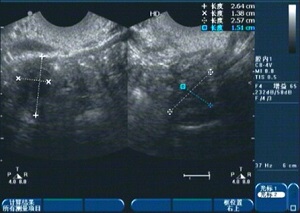

小林先后到过北京、广州、深圳等多地医院求医,均没有达到理想效果。2014年,小林又打听到杭州红房子妇产医院能治疗幼稚子宫,她抱着试一试的心态来到杭州。石女之母费旭红主任通过阴道四维彩超检查,提示:幼稚子宫。垂体兴奋实验检查提示:低促性腺性功能低下。费主任说:这个病是可以治疗的!